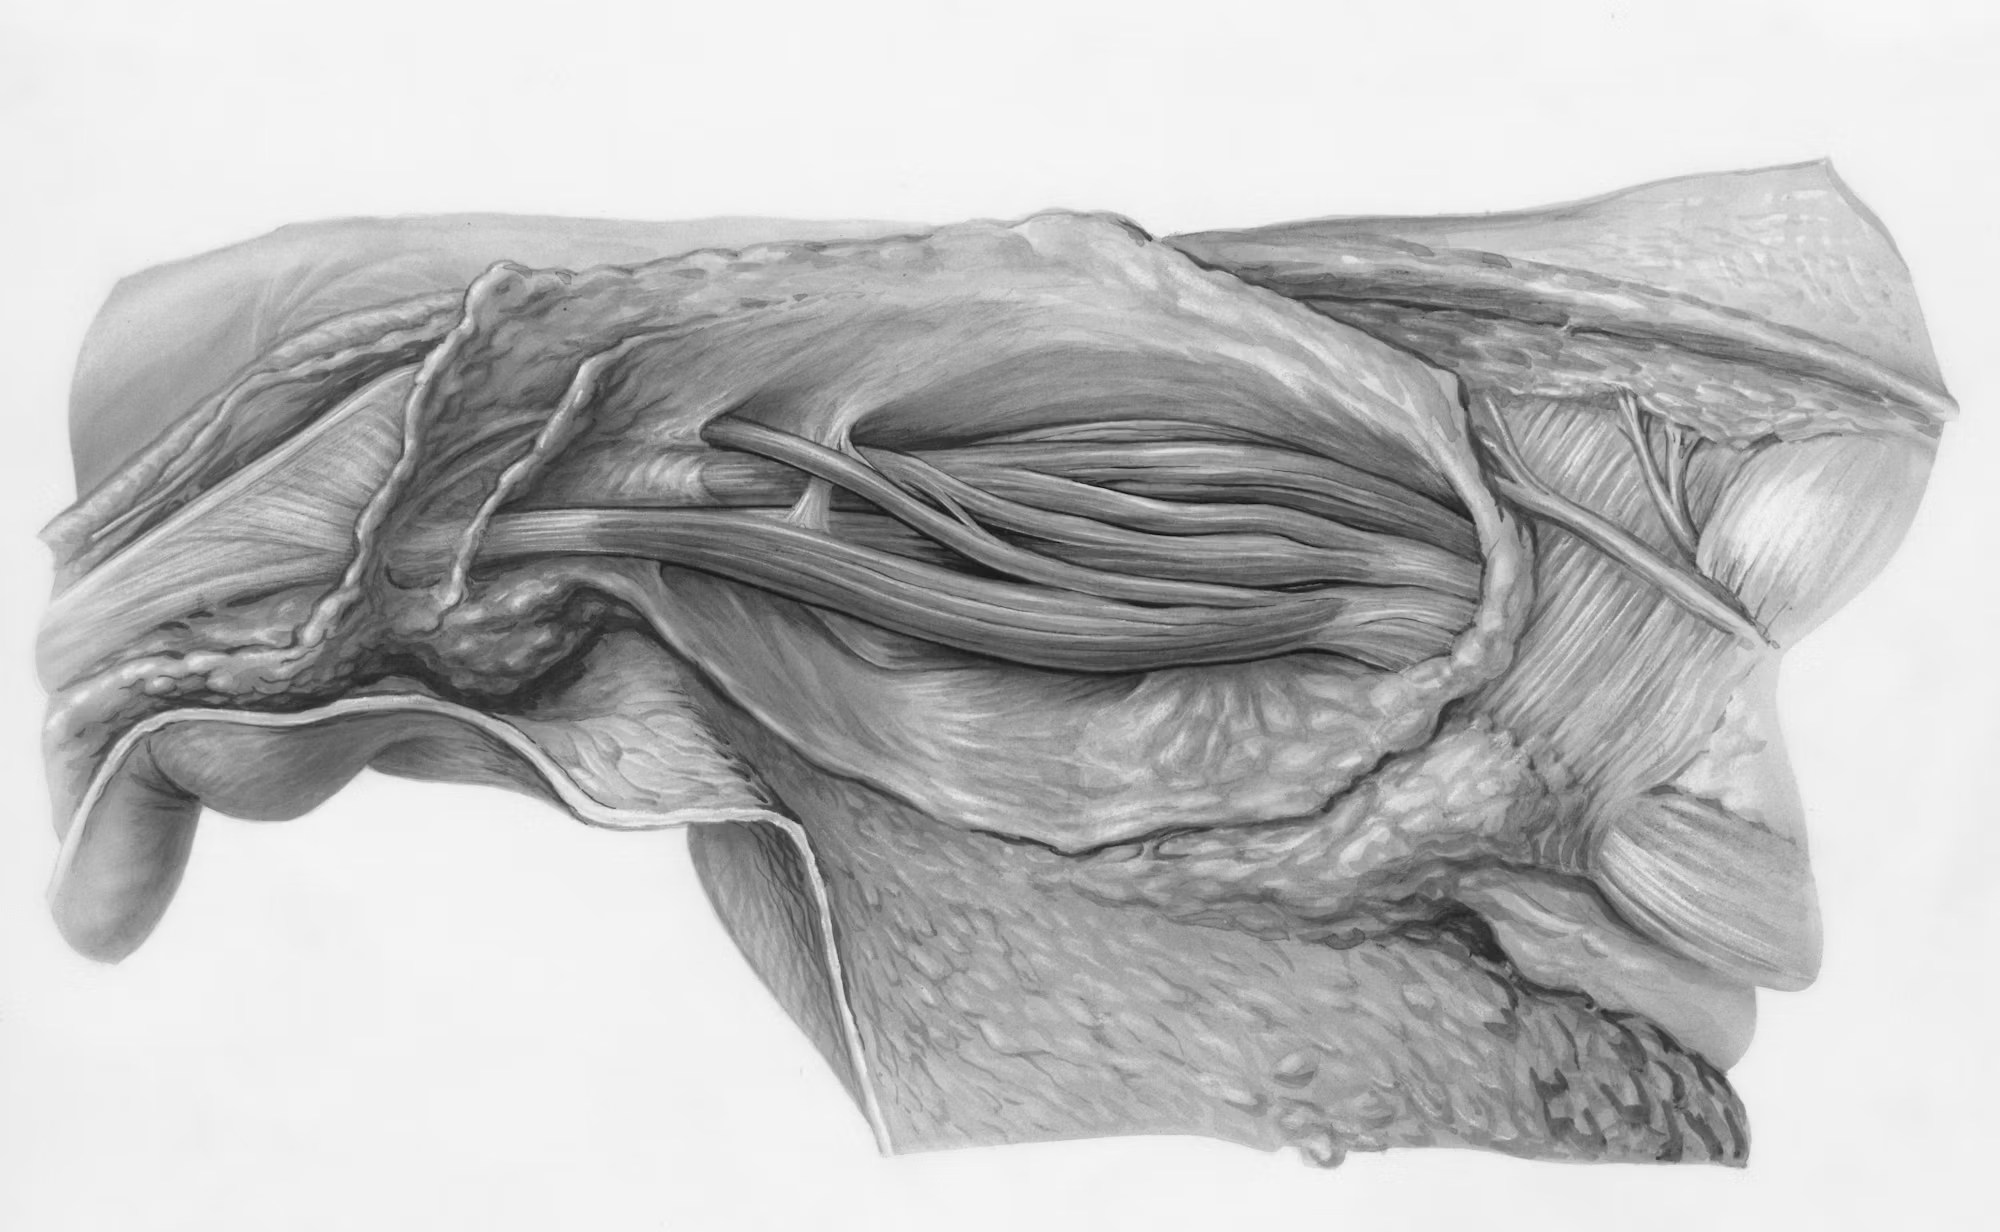

An insightful exploration of how medical education has evolved over the centuries, focusing on how h